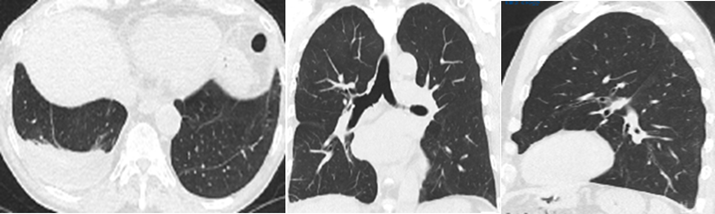

1. A 67-year-old man presented with chronic cough and progressive dyspnea.

2. He had a medical history of chronic sinusitis and gastroesophageal reflux disease (GERD).

3. Chest CT was performed for further evaluation.

4. He was diagnosed with acute hypoxic respiratory failure.

Findings and Diagnosis

Rapidly progressive fibrosing interstitial lung disease. Marked subpleural and bilateral basal traction bronchiectasis, honeycombing, and irregular reticular opacities suggest an atypical UIP pattern/idiopathic pulmonary fibrosis.

Imaging Features

IPF is radiologically defined by a usual interstitial pneumonia (UIP) pattern in the absence of a known cause. High-resolution computed tomography (HRCT) typically reveals subpleural and posterior basal predominance of honeycombing, reticular septal thickening, and traction bronchiectasis. These findings are characteristic of UIP and support the diagnosis of IPF.